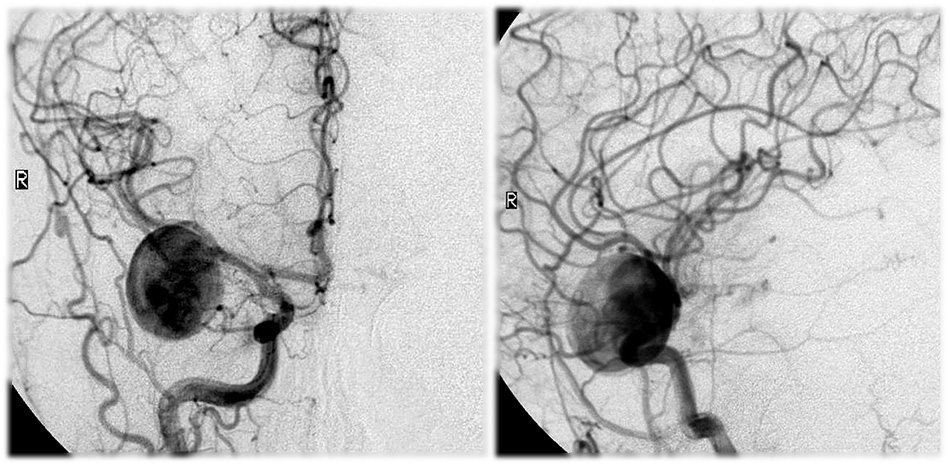

Снимки и иллюстрации микроаневризм сосудов головного мозга